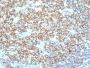

Positive Control

Daudi, Raji, and U266, and human lymphocytes. Lymph nodes and tonsils.

This antibody recognizes a protein of 30-33 kDa, which is identified as CD20. It is a non-Ig differentiation antigen of B-cells and its expression is restricted to normal and neoplastic B-cells, being absent from all other leukocytes and tissues. CD20 is expressed by pre B-cells and persists during all stages of B-cell maturation but is lost upon terminal differentiation into plasma cells. This MAb can be used for immunophenotyping of leukemia and malignant cells, B lymphocyte detection in peripheral blood and B cell localization in tissues. It reacts with the majority of B-cells present in peripheral blood and lymphoid tissues and their derived lymphomas. In lymphoid tissue, germinal center blasts and B-immunoblasts are particularly reactive. It is a reliable antibody for ascribing a B-cell phenotype in known lymphoid tissues. Rarely, CD20-positive T-cell lymphomas have been reported. Reactivity has also been noted with Reed-Sternberg cells in cases of Hodgkin's disease, particularly of lymphocyte predominant type.Primary antibodies are available purified, or with a selection of fluorescent CF® Dyes and other labels. CF® Dyes offer exceptional brightness and photostability. Note: Conjugates of blue fluorescent dyes like CF®405S and CF®405M are not recommended for detecting low abundance targets, because blue dyes have lower fluorescence and can give higher non-specific background than other dye colors.